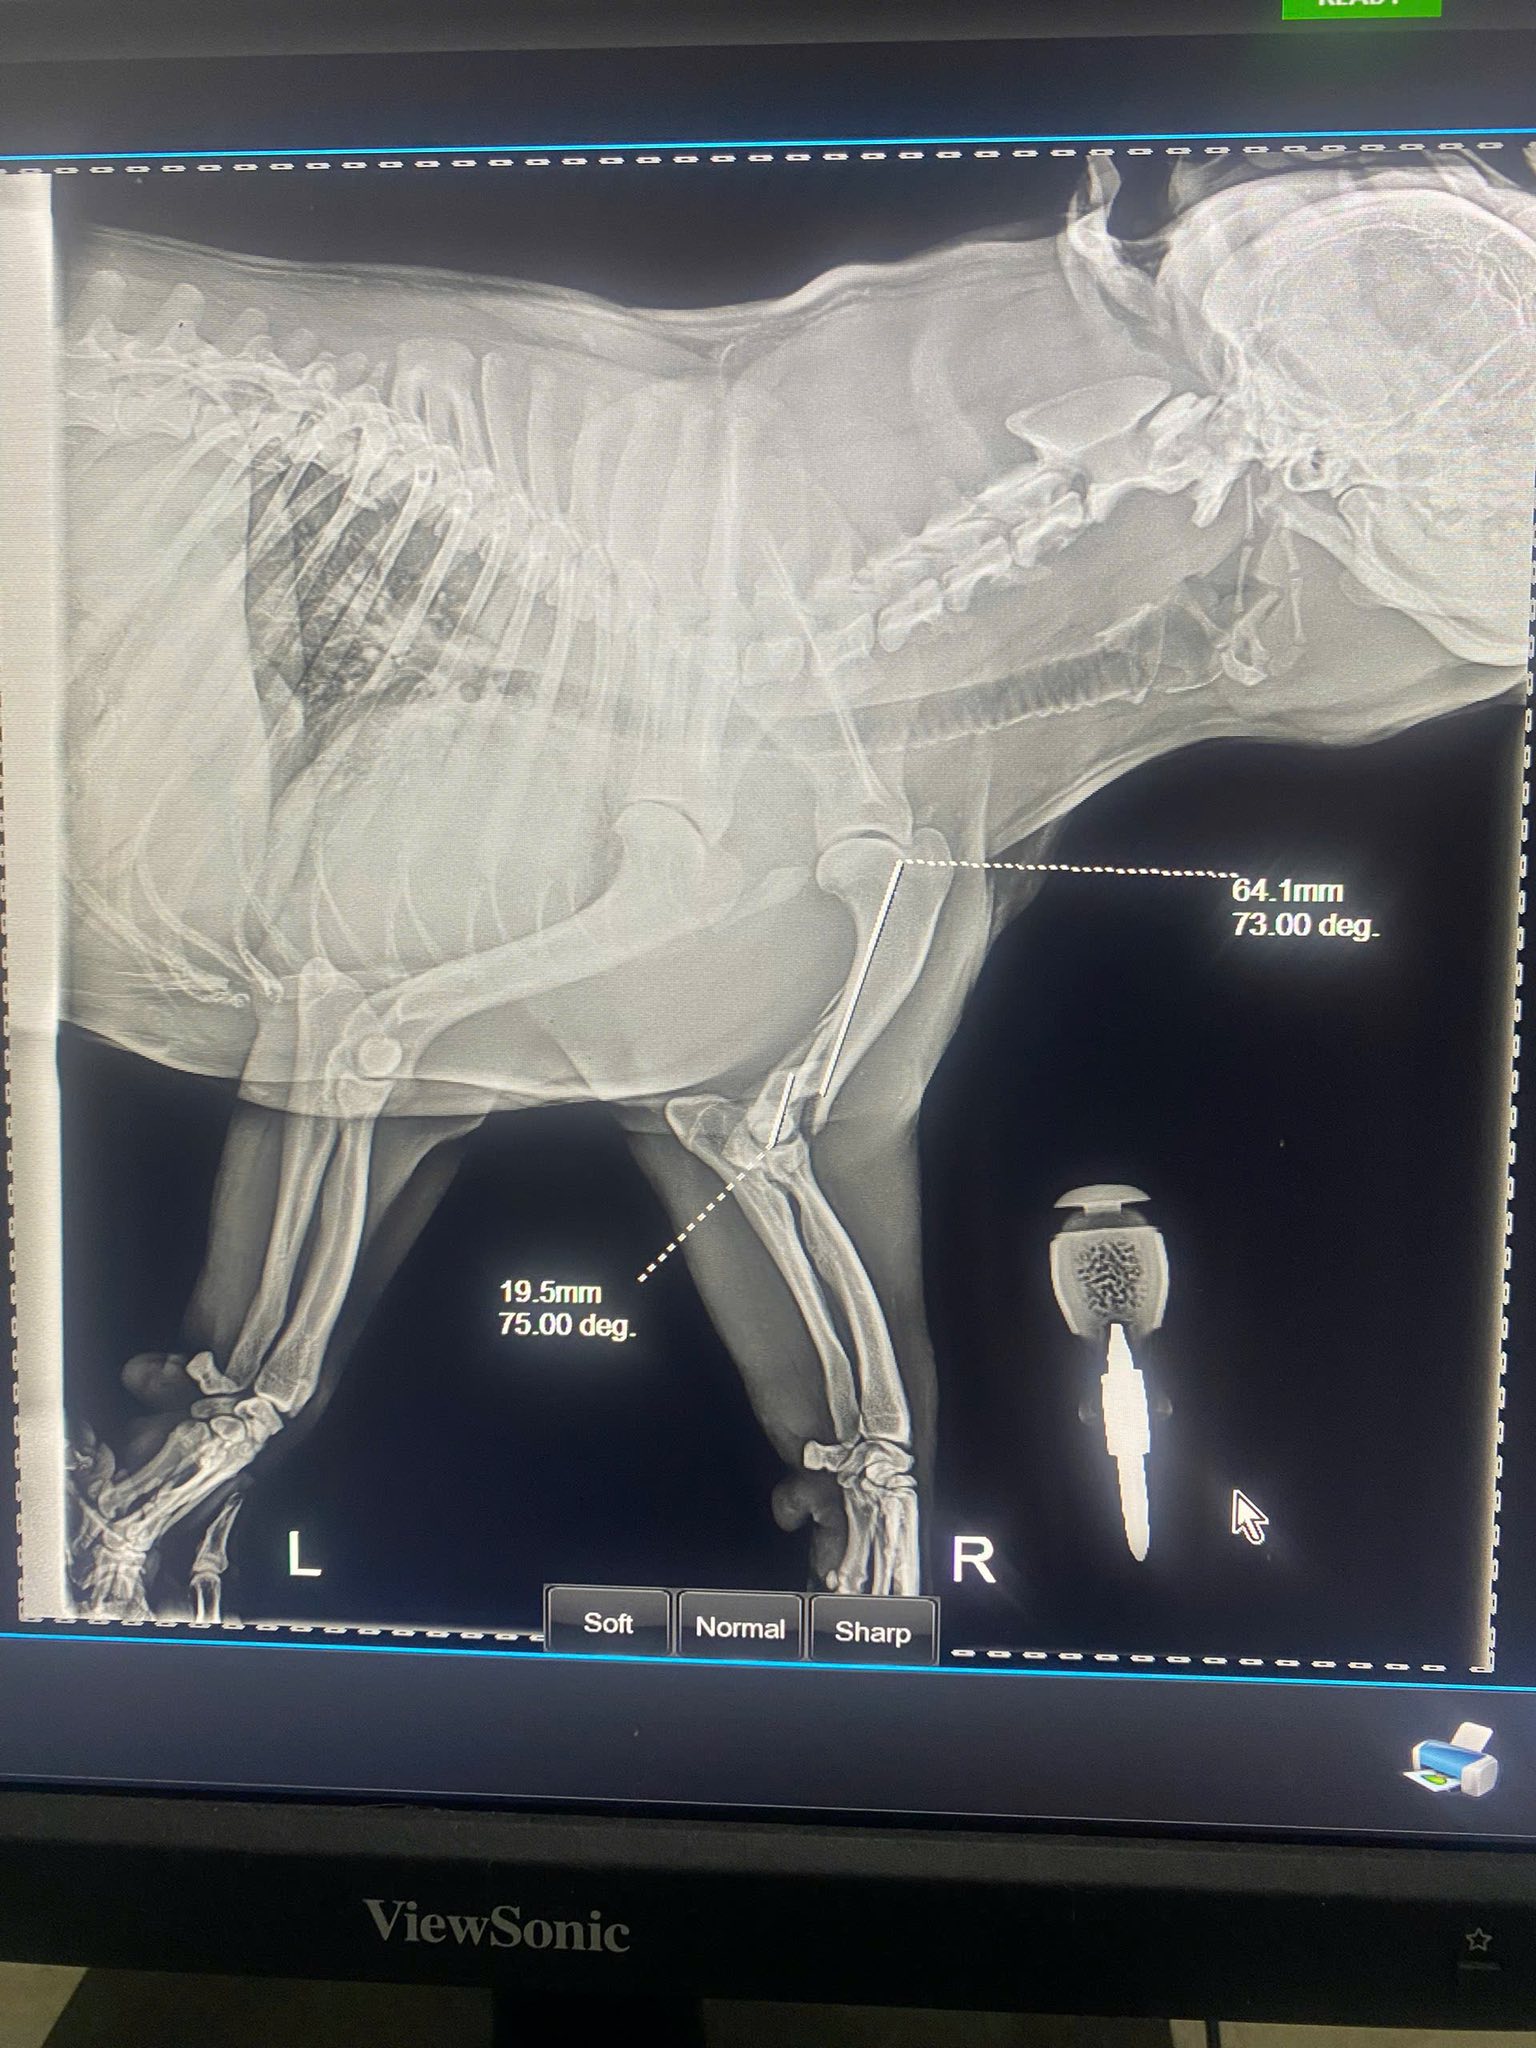

He needs X-rays to rule out fractures, wound debridement, follow-up treatments, and weeks—if not months—of rehab.